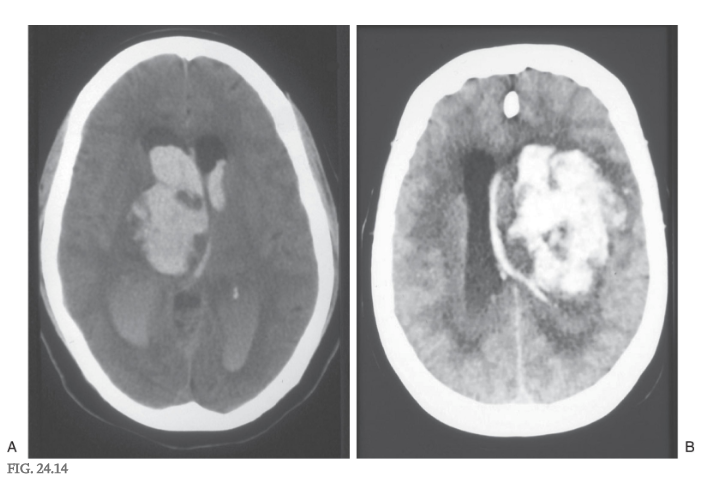

Decortication

A second type of posturing frequently observed in human patients is referred to as decorticate posturing or decorticate rigidity ( Figs. 24.9D and 24.10D ). The clinical events that lead to this type of posturing are frequently large lesions of the cerebral hemisphere ( Fig. 24.14 ). These may be vascular or rapidly growing tumors that are located in one hemisphere, damage major tracts on that side, efface the midline, and compromise tracts on the opposite side by mass effect and compression. The net result is a removal of cortical influence on brainstem motor nuclei.

In the clinic, the patient presents with flexion of the upper extremities (intact rubrospinal fibers) at the elbow combined with extensor hypertonus in the lower extremities (intact reticulospinal fibers), an altered state of consciousness and respiration, oculomotor deficits, and a range of motor responses from weakness to motionless ( Fig. 24.15 ).